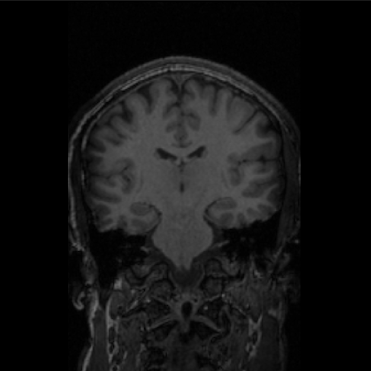

I used the Maker Hub 3D printers to print out a 1:1 scale model of my own brain after getting an MRI this past summer. Additionally, I printed the brains of about 26 participants in a neuroimaging study I was a research assistant for during Summer 2018. 3D printing helped facilitate my research by providing our 9-13 year old participants with scale models or their individual brains, both providing them with a physical reminder of the study and allowing them to feel involved.